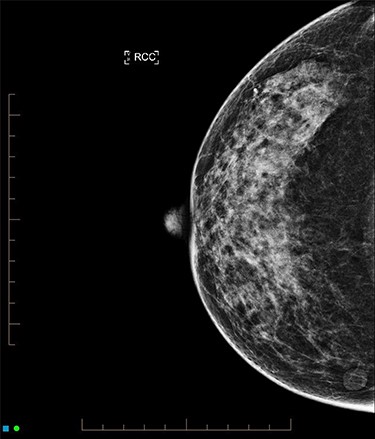

An ultrasound of the left breast demonstrated a 60-mm irregularity with no underlying collection at the 10 O’clock position, 2 cm from the nipple (Fig. 1). AB was treated with 5 days of oral flucloxacillin for presumed mastitis, and underwent a bilateral mammogram and ultrasound due to the suspicious irregularity of the left breast lesion. This showed an area of asymmetric density in the medial left breast with hyperemia (Fig. 2). The right breast showed two clusters of pleomorphic microcalcifications in the upper outer quadrant, further characterized as irregular lesions measuring 16 × 11 × 11 mm and 9 × 10 × 7 mm (Fig. 3).